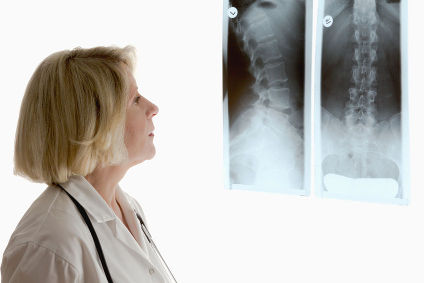

La radiologia è una disciplina medica essenziale che utilizza le tecnologie delle immagini diagnostiche per esplorare l’interno del corpo umano. Attraverso l’impiego dello strumento ecografico presso la nostra struttura, la radiologia fornisce agli specialisti una visione dettagliata per la diagnosi, la gestione e il monitoraggio delle condizioni mediche.

Ecografia del collo Ecografia tessuti molli ecografia osteoarticolare ecografia muscolo tendinea ecografia addome superiore ecografia addome Inferiore ecografia addome completo